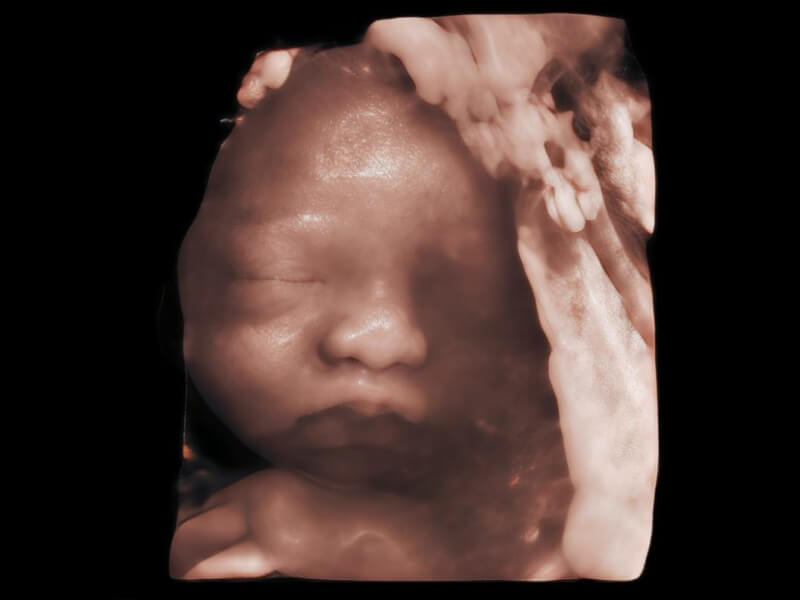

HD Portrait

Image quality always lies at the core of definitive clinical outcomes. The P80 Elite introduces evolutional transducers with excellent 2D image clarity and color sensitivity for more confident assessment in anatomy and pathology.